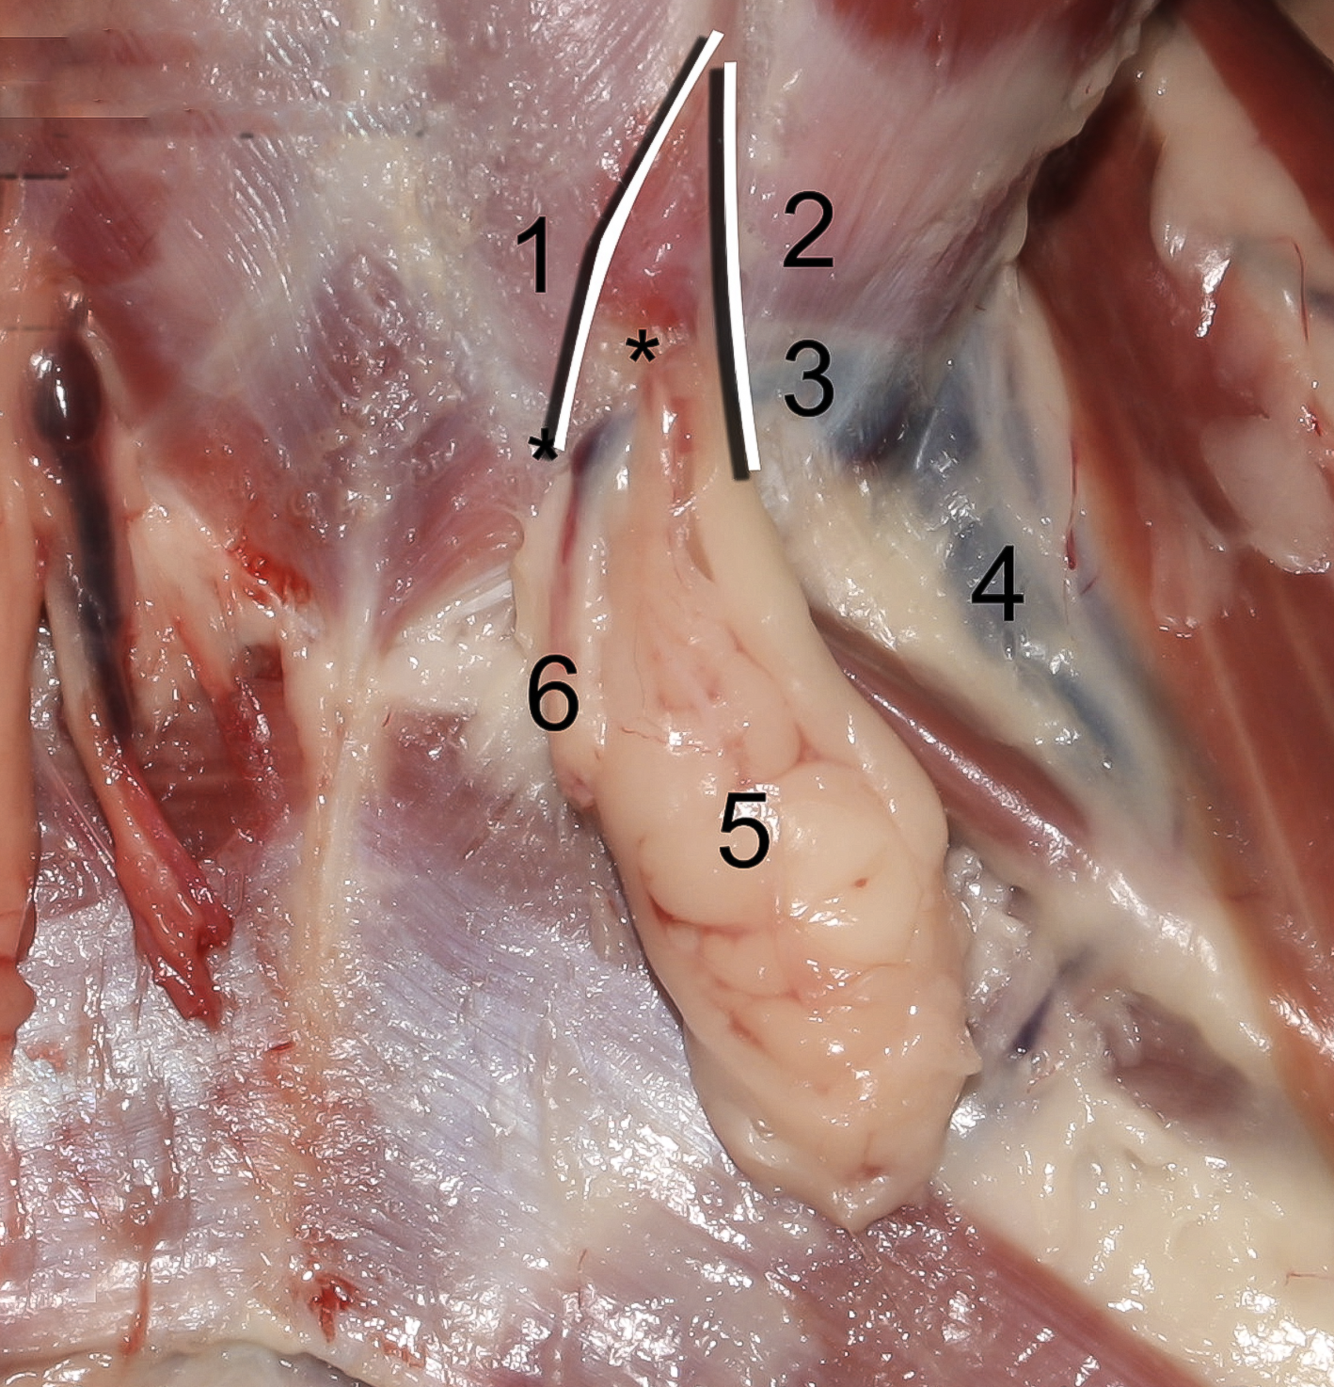

19

Q

13

A

A./v. pudenda externa

- Through canalis inguinalis

- Branches: a. epigastrica caudalis superficialis

20

Q

15

A

A. epigastrica caudalis

- Supplies m. rectus abdominis

- Through canalis inguinalis

- Branches:

- **A. labialis/scrotalis ventralis

25

**Anulus inguinalis superficialis**

26

**M. obliquus internus abdominis**

27

**M. obliquus externus abdominis**

28

**Tunica vaginalis**

29

**Proc. vaginalis**

30

**Lig. teres uteri**